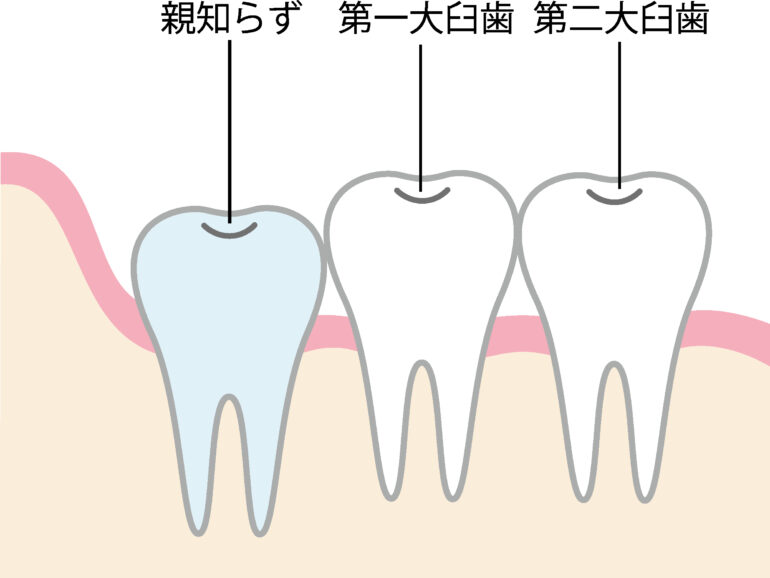

まっすぐキレイに生えている状態。完全埋伏智歯

歯ぐきの中に完全に埋まってしまっていて表面には出ていない、見えない状態です。親知らずがある部分が腫れている、痛みがある、他の歯や顎関節への影響がある場合は抜歯を検討する必要があります。

歯ぐきの中に完全に埋まってしまっていて表面には出ていない、見えない状態です。親知らずがある部分が腫れている、痛みがある、他の歯や顎関節への影響がある場合は抜歯を検討する必要があります。水平埋伏智歯

3. 完全に埋まっていて、他の歯に影響がない親知らず

親知らずが完全に歯ぐきの中に埋まっている「完全埋伏智歯」の場合も、他の歯に影響を与えていなければ、無理に抜く必要はありません。完全に埋まっている状態では、親知らずが痛みや腫れを引き起こすことが少なく、問題が発生しない限り、そのまま保存しても問題ないことがあります。ただし、嚢胞(のうほう)などの問題が発生する可能性もあるため、定期的な診断が重要です。